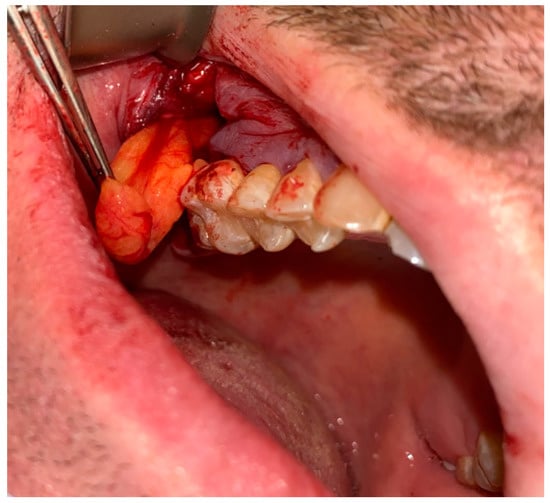

Figure 3. The bone defect was covered with the Bichat fat pad after mobilization. The entire defect will be sutured with vertical mattress sutures to the palate to ensure its proper position.